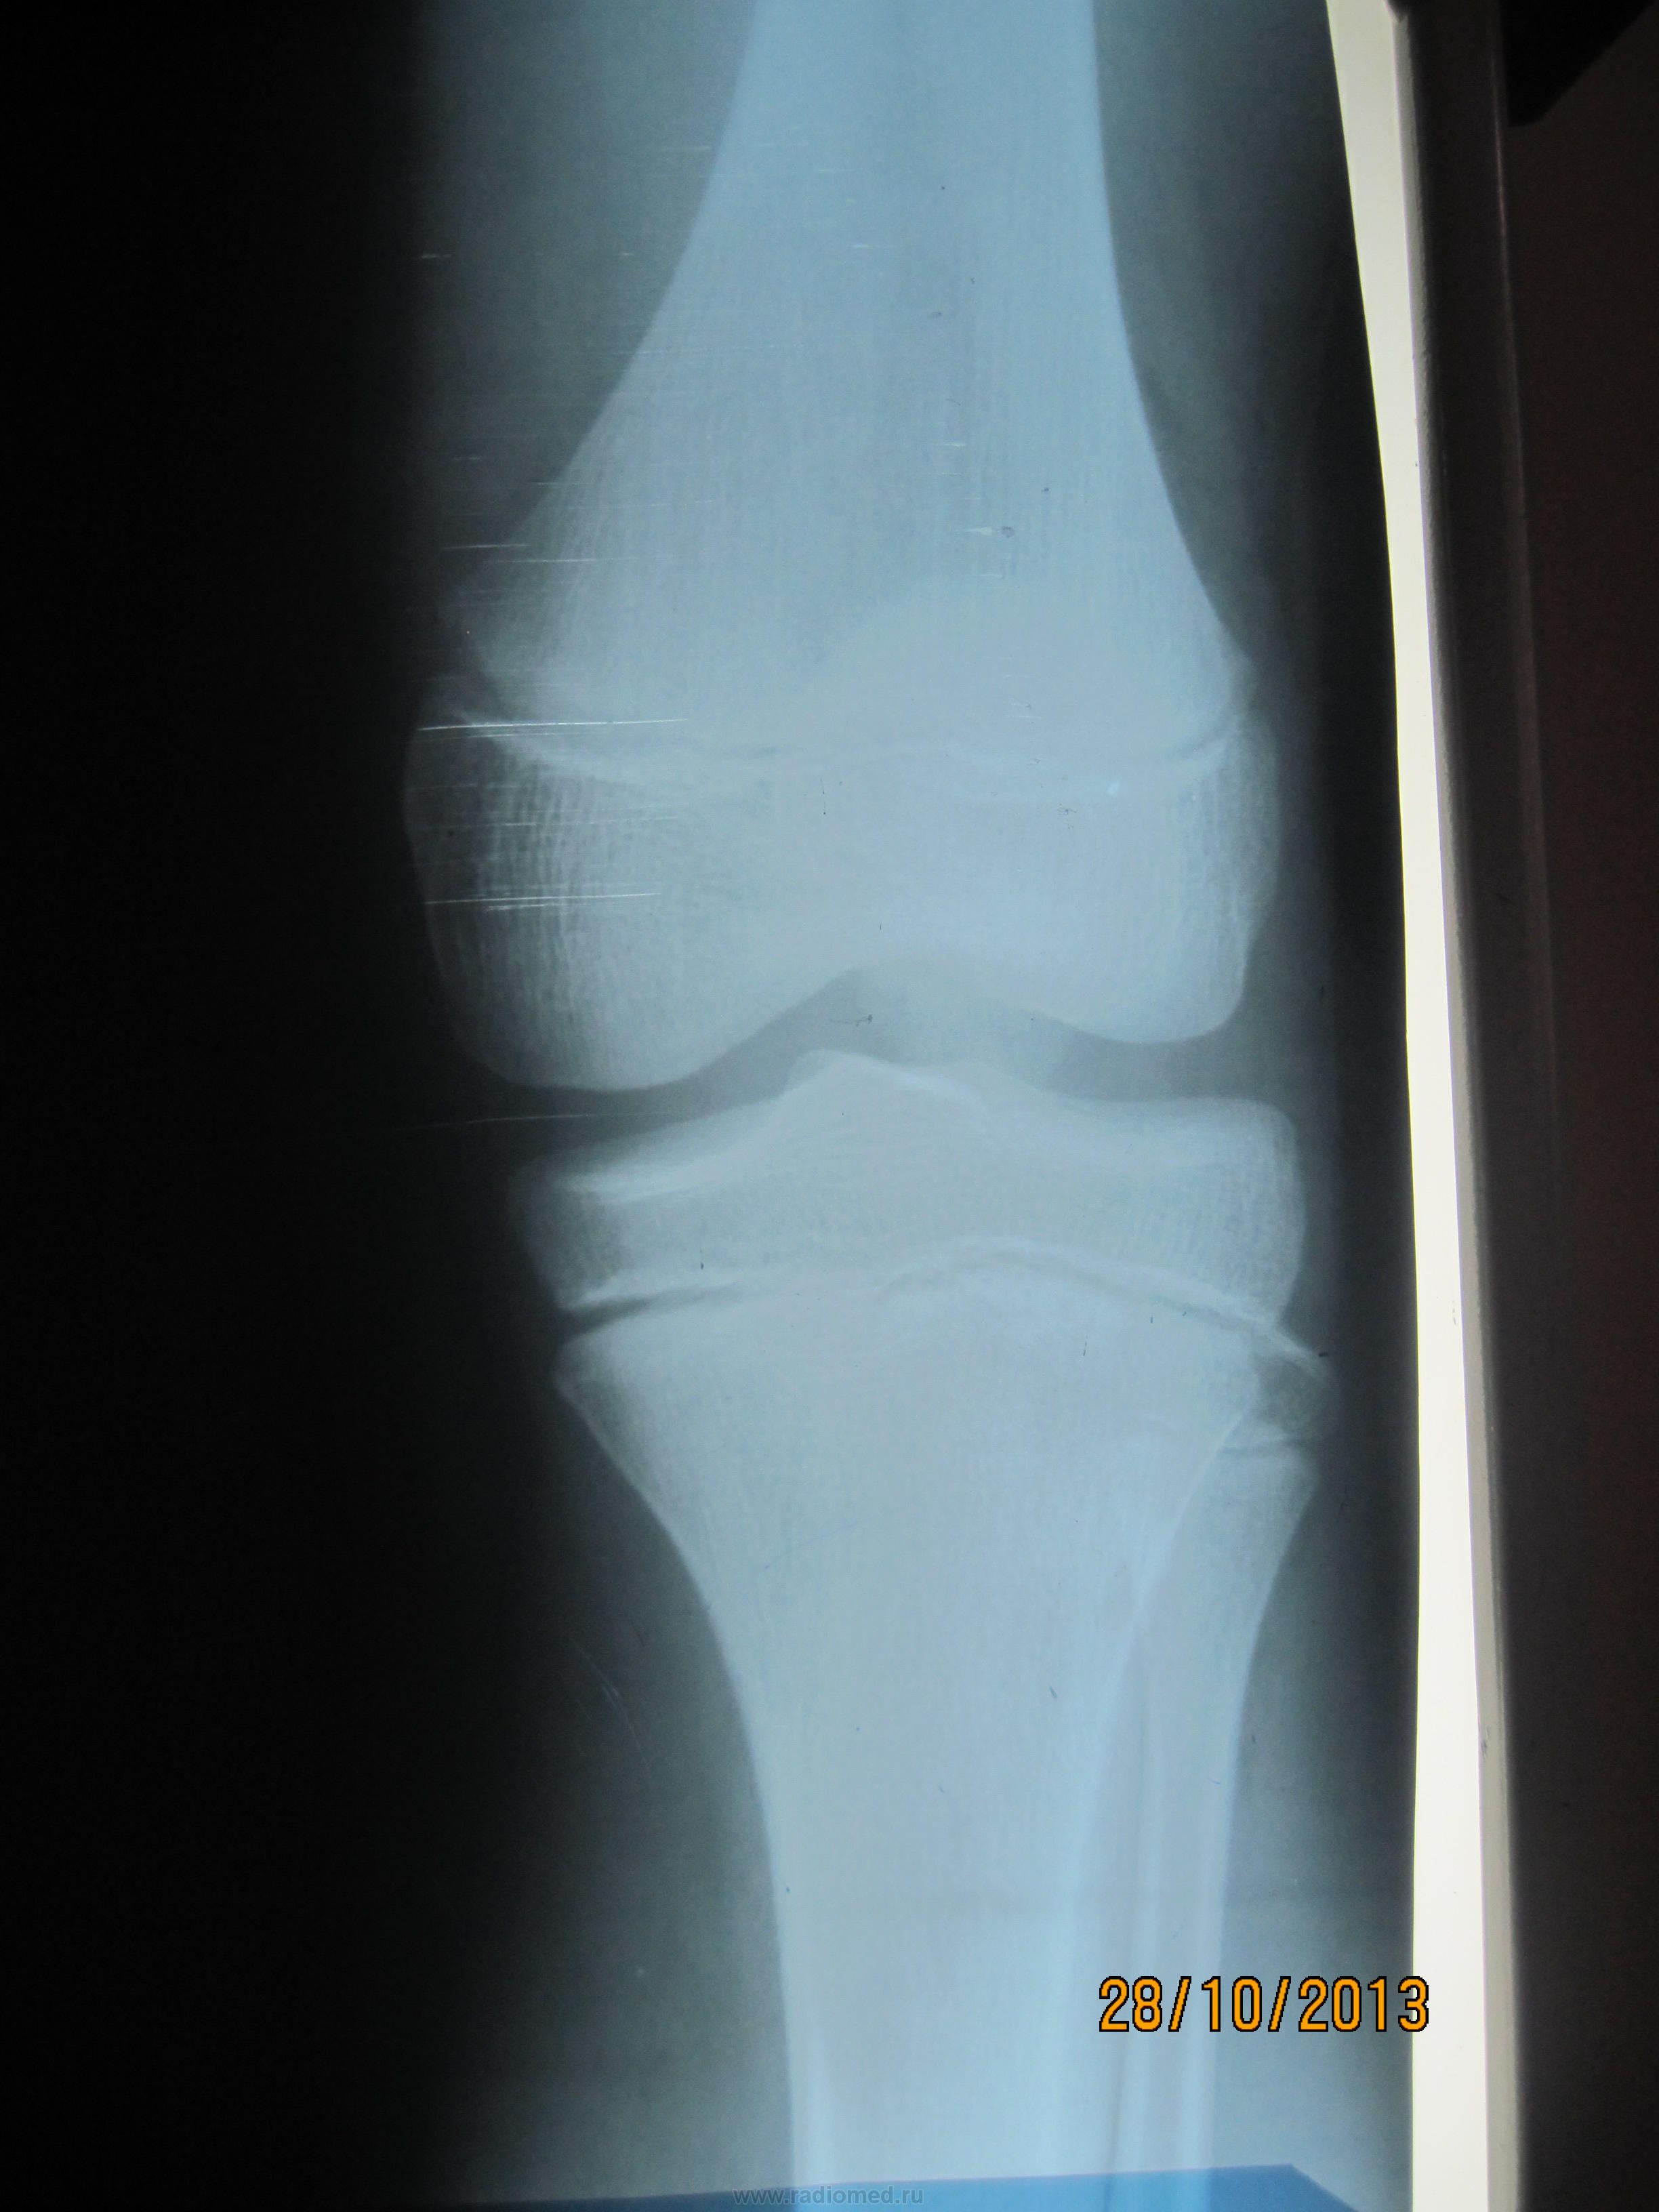

Всё узнала - болен в течении 1недели, жалобы на нарушение походки ( прихрамывание на левую ногу), Т37,2, умеренная болезненность при пальпации нижней части надколенника, и при сильном сгибании. Визуально симметричны = 32см, отечности и гиперемии нет. Узи левого коленного сустава- отечность мягких тканей, минимальное кол-во жидкости не требующее пункции. З-е: Косвенные узи признаки левостороннего артрита.

Такое ощущение, что бугристость болшеберцовой кости фрагментирована справа.

Где покажите стрелочкой пожалуйста? И что нам это даёт?

Не похоже, чтобы тянул левый коленный сустав на артрит.

А на Осгуд-Шлаттера не тянет слева?